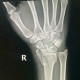

Alo dok, saya ada kenalan pasien yg kemarin mengalami KLL jatuh dari motor dengan lengan kanan menghantam aspal dan jatuh sekitar 3 meter dari motor. Sudah di rontgen IGD dan didapatkan Fraktur komplit comminuted radius distal dengan angulasi volar. Meskipun sudah diedukasi berulang kali, keluarga pasien bersikeras tidak mau dioperasi secepatnya.

Menurut dokter, bagaimana cara menjelaskan ke pasien ya dok, mereka ttp menginginkan di urut terlebih dahulu. Mohon sarannya dok, thanks